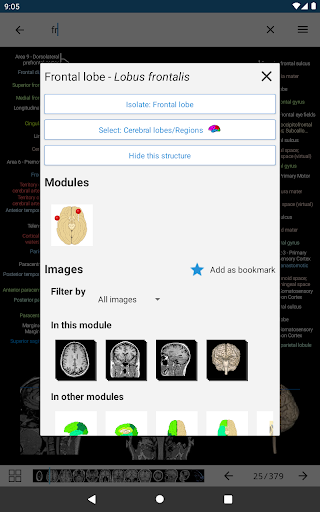

*Improved detail view of anatomical parts for easier identification in images of the current and other modules.

-Within the details view of an anatomical structure, a pin now points the related structure in all present images

Also tap directly on the image to navigate to the presented image in that module

- “Filter by”, in the details view you can now filter the images containing the anatomical structure by modality

- “Filter by”, in the details view you can now filter the images containing the anatomical structure by modality